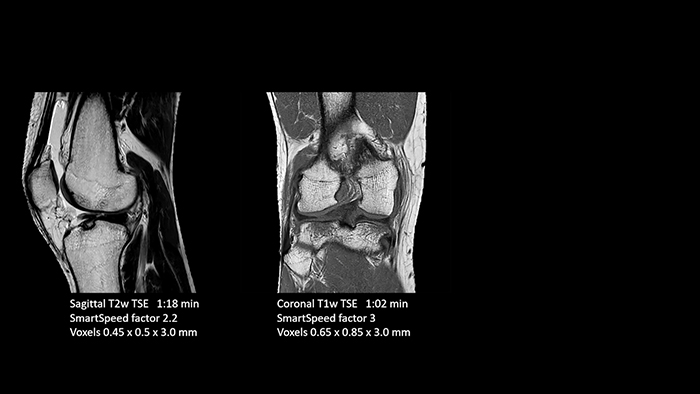

A leap in MSK imaging thanks to SmartSpeed

Previously, the practice wasn’t able to use 3D imaging on all joints, because the time required was too long, and on some joints it was simply not possible to achieve a good quality image, Dr. Schröter says. “Now, with SmartSpeed we consistently use 3D imaging for all joints and can thus discover the smallest changes, for example in the cartilage. And that, of course, helps us in making a detailed diagnosis.” Dr. Schröter says their MSK images show high contrast and extremely high quality. He mentions the menisci as an example. “We use a 3D proton density weighted fatsat sequence, thickness is 0.3 mm and scan time 3 minutes. The MPRs show an unbelievable resolution. Very small tears and even fraying of the tip of the meniscus become visible, which is normally only possible in arthroscopic surgery. When imaging the small joints of the fingers and the thumb we achieve extraordinary quality. Using SmartSpeed we succeed in displaying even very small structures anatomically correct, enabling us to see the extent of possible injuries. Tendons and ligaments appear with higher resolution so we can better see the injury pattern and describe and delimit it. Our referring physicians are fascinated by the extraordinary quality and high level of detail of the images. Patients are happy that the examination does not take too long. We hear from patients that it took a lot less time than they expected. This is especially important when scanning patients who are very uncomfortable in the MRI environment.”

- Traumatic knee injury

SmartSpeed is used to reduce scan times. All three PDw orientations were obtained with only one 3D sequence using SmartSpeed. Performed with 1.5T Ambition X, 16ch dS Knee coil.

- Traumatic knee injury

SmartSpeed is used to reduce scan times. All three PDw orientations were obtained with only one 3D sequence using SmartSpeed. Performed with 1.5T Ambition X, 16ch dS Knee coil.

With these 3D scans we can create freely selectable MPRs that are pin-sharp, allowing us to easily see pathological changes.”